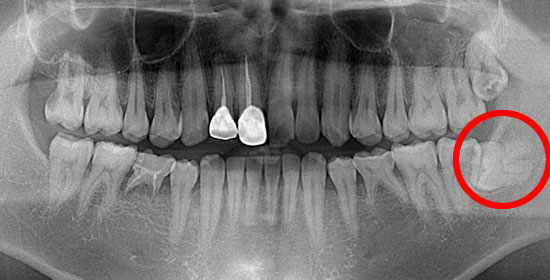

↓のように横向きに生えていると、7番目の歯と親知らずの隙間に細菌が溜まり、虫歯になったり、周囲の歯肉が腫れたりする原因となります。

術前

上下左右4本の親知らずがそれぞれ生えていますが、下の親知らずの抜歯は特に注意が必要です。この様に横に生えている親知らずと下顎管が近接している場合、下顎管にダメージを与えると、下唇や顎付近に知覚異常・鈍麻が起こる場合があります。また、抜歯の際、舌神経を傷つけると舌の痺れ等が起こる場合がありますので、抜歯の際は細心の注意が必要です。